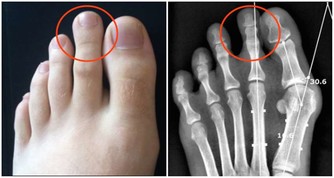

下肢青筋——靜脈曲張 小腿有青筋,即我們所說的下肢靜脈曲張,需要長時間站立或體力勞動較重的人容易出現這種情況,開始往往沒有任何疼痛症狀出現,但可以見到青筋,需要引起重視。常見不適表現為疼痛,嚴重者會出現下肢腫脹、潰瘍、出血等症狀。 調理方法:1.如果在治療時只是輕度的疼痛,可以適當地使用紅花、艾葉泡腳,緩解疼痛症狀。2.若出現嚴重的疼痛則需要及時到醫院綜合治療,採用血府逐淤湯、桃紅四物湯等中藥都可以很好地活血化淤止痛。